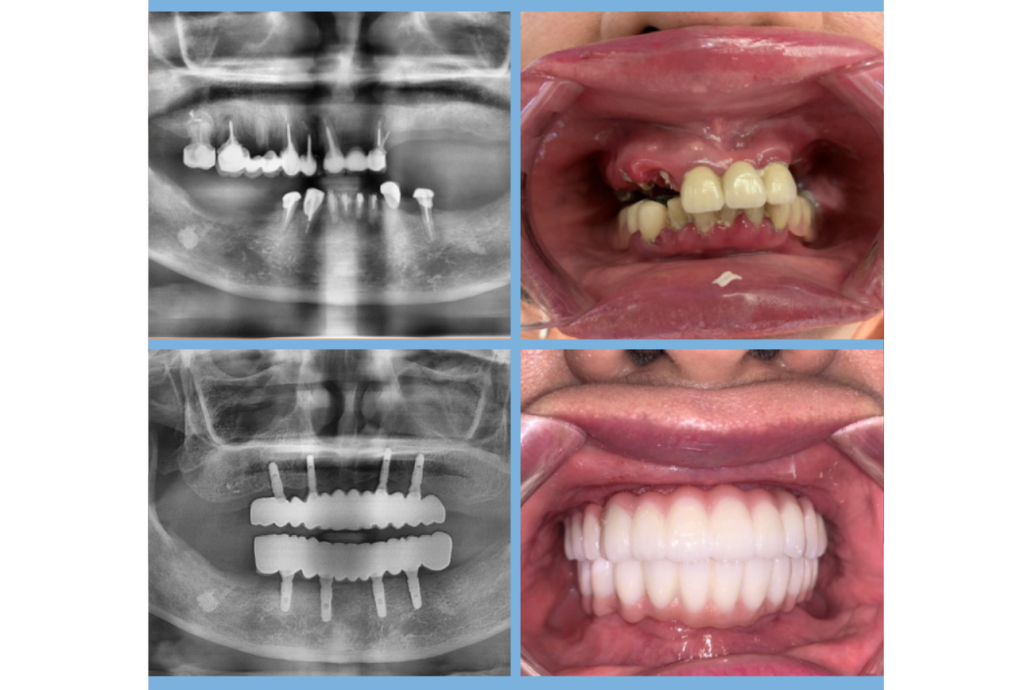

微創植牙 小傷口,大改變 結合3D導引技術與數位影像分析,手術精準、恢復快速,讓植牙更安全、舒適。 立即預約諮詢 全程專屬規劃 為你打造精準、安全的植牙體驗 全程數位導引,讓植牙更精準、更安心。 全口檢查與影像評估 透過X光與3D斷層掃描,完整了解骨質厚度、神經與上顎竇位置,確保手術安全。 數位植牙規劃 運用電腦軟體模擬植體角度與深度,並製作專屬導引板,提高手術精準度。 微創手術植入 僅需微小切口即可完成植體植入,出血少、疼痛低、恢復快。 骨整合癒合期 約2–4個月內,人工牙根與齒槽骨結合穩定,為後續牙冠裝戴做準備。 安裝人工牙冠 依據牙齒形狀製作全瓷或混合式牙冠,恢復自然咬合與美觀。 定期回診與保養 每3–6個月回診檢查,確保植體健康與牙周穩定,延長使用壽命。 精準・安全・快速恢復 專業團隊陪你重建自然笑容 從數位影像評估、手術規劃到人工牙冠裝戴,全程由植牙專科醫師親自操作。透過3D導引技術與數位導航,降低風險、縮短恢復期,讓植牙更安心。 3D導引定位: 精準掌握角度與深度,減少術中誤差。 數位影像分析: 即時模擬植體位置與咬合狀況。 專業醫師操作: 全程由原醫師執行與追蹤。 傷口小恢復快: 出血少、腫脹低,日常生活不受影響。 植牙流程超簡單 三步驟,重拾自然咬合與自信笑容 1 精準評估與3D規劃 透過電腦斷層與3D導引軟體,分析骨質與神經位置,量身制定植牙方案。 2 微創手術植入 在數位導引板輔助下完成植體植入,傷口小、出血少、恢復快。 3 安裝牙冠與定期追蹤 待骨整合完成後裝上全瓷牙冠,醫師定期檢查確保穩定與美觀。 患者見證 他們的笑容,證明一切 微創植牙不只是補回缺牙,更讓生活重拾自信與笑容。 王先生上顎單顆植牙患者 ★★★★★ Rated 5 out of 5 「手術比想像中輕鬆許多,術後幾乎沒腫、沒痛。現在吃東西也完全恢復正常,真的很推薦微創植牙!」 李小姐全口重建患者 ★★★★★ Rated 5 out of 5 「醫師用3D導引幫我設計植牙位置,整個手術過程非常安心。恢復期短、效果自然,看起來就像真牙一樣!」 張先生長期缺牙患者 ★★★★★ Rated 5 out of 5 「之前一直怕傳統植牙太痛,沒想到微創手術只花了不到一小時,隔天就能正常上班,真的太神奇了!」 成功案例 0 + 病患滿意度 0 /5 療程成功率 0 % 開始之前,你一定想知道的事 為什麼越來越多人選擇微創植牙?傷口小、恢復快:手術時間短、術後腫脹與疼痛感低。出血量少:過程精準穩定,對中老年與慢性病患者更安全。美觀自然:牙齦完整度高,外觀幾乎與真牙無異。精準導引:3D導航技術避開神經與血管,降低風險。生活便利:術後可快速恢復進食與日常活動。 Q1. 微創植牙會痛嗎? 微創手術僅需小切口或免翻瓣操作,出血少、傷口小。手術過程中有局部麻醉,幾乎無疼痛感,術後僅輕微腫脹不適,1–2天內即可恢復。 Q2. 微創植牙需要多久? 單顆植牙手術時間約30–60分鐘,術後2–4個月骨整合完成後即可裝上牙冠。若條件良好,部分患者甚至能當天植牙+裝臨時牙。 Q3. 誰適合做微創植牙? 牙齦健康、骨質條件足夠者最適合。若骨量不足或有慢性病,醫師會先評估再建議是否可行。 Q4. 微創植牙比傳統植牙好在哪? 微創手術切口小、恢復快,幾乎無明顯腫脹。同時透過3D導引定位,手術更精準、安全。 Q5. 植牙可以用多久? 在良好保養下可使用15–20年以上,甚至終身。定期回診與良好的口腔清潔是延長壽命的關鍵。 想了解更多?立即預約諮詢! 由專業醫師親自評估你的牙齒狀況,為你規劃最合適的方案,展現自然又自信的笑容。 立即預約諮詢